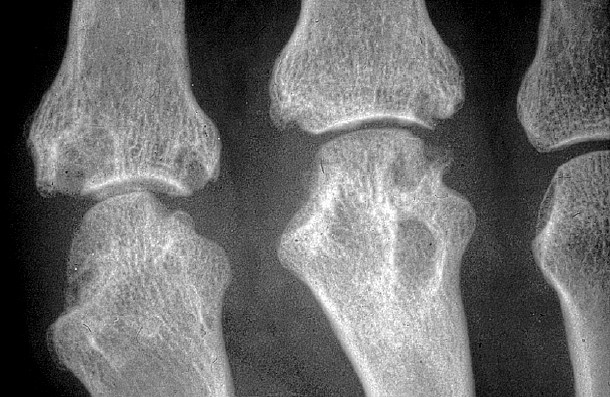

Les signes de rhumatisme inflammatoire périphérique se traduisent au début par un simple gonflement des parties molles (synovite) puis par une déminéralisation métaphysoépiphysaire « en bande », des érosions épiphysaires, un pincement irrégulier mais global de l’interligne articulaire et des géodes souschondrales (destruction articulaire) (figure 1.2).

Fig. 1.2. Aspect radiographique de polyarthrite rhumatoïde. Érosions rhumatoïdes caractéristiques des articulations des doigts traduisant l’agressivité de la synovite rhumatoïde